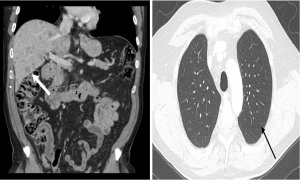

A 69-year-old man presented to a tertiary hospital with a three-month history of right upper quadrant abdominal pain and a 30-pound weight loss. Apart from hypertension, his medical history was otherwise non-contributory, and he had no relevant family history or notable psychosocial factors. A whole-body CT scan demonstrated numerous hepatic lesions along with a vertebral sclerotic lesion, raising concern for metastatic disease, with no evidence of cirrhosis (Figure 4).

After review with medical oncology, he was started on palliative carboplatin and etoposide chemotherapy. His prognosis was deemed poor with an expected survival of less than 3 months without therapy and 12 months with chemotherapy. The patient tolerated 6 cycles of carboplatin and etoposide with a repeat CT scan demonstrating stable mild reduction in liver metastasis and progression of bony metastatic disease. Unfortunately, after a brief 4-week treatment break, the patient had clinical and radiographic evidence of disease progression, and thus he was started on another 4-6 cycles of carboplatin and etoposide. He was also referred to radiation oncology for consideration of palliative radiation for disease control/symptom management of his diffuse bone disease. The patient died 11 months after diagnosis.